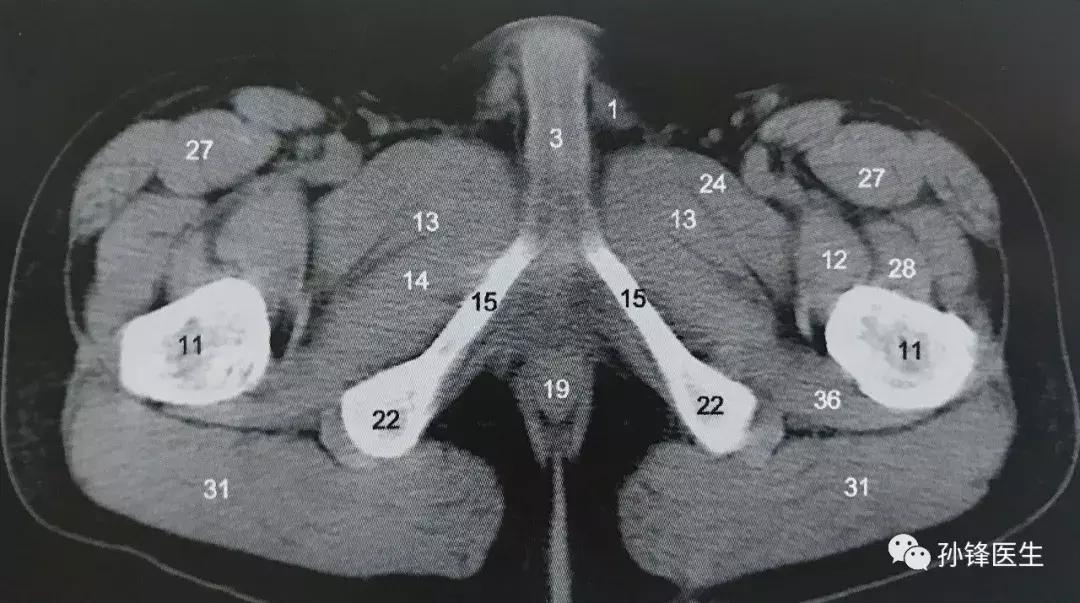

注意:坐骨耻骨支是十分重要的影像学定位标志,我们一起来看一张CT影像,如下图(16)↓↓↓。

图(16):图中标记点“15”即为坐骨耻骨支↑↑↑